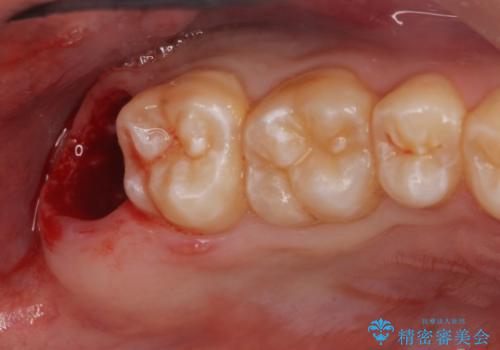

- 右上下親知らずを抜きたいとの事で来院。

レントゲンを確認したとこと完全埋伏歯でした。

CTで神経の位置などを確認し、抜歯術を行いました。

無事抜歯を行うことができました。

1週間後に傷口チェックと抜糸を行う必要があります。